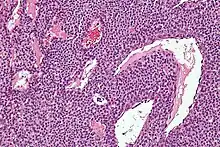

Micrograph of a glomus tumor. H&E stain.

Histologically, glomus tumors are made up of an afferent arteriole, anastomotic vessel, and collecting venule. Glomus tumors are modified smooth muscle cells that control the thermoregulatory function of dermal glomus bodies. As stated above, these lesions should not be confused with paragangliomas, which were formerly also called glomus tumors in now-antiquated clinical usage. Glomus tumors do not arise from glomus cells, but paragangliomas do.

By histopathology, glomus tumors can be termed as follows:[7]

• Solid glomus tumor (75% of cases): Consisting predominantly of glomus cells, with poor vasculature and rare smooth muscle cells.

• Glomangioma (20% of cases): Tumors with a prominent vascular component.

• Glomangiomyoma (5% of cases): Tumors with prominent vascular and smooth muscle components.